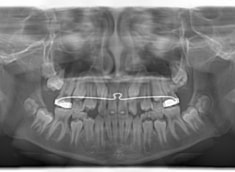

小児期ケース:反対咬合+上顎両側3番埋伏歯

(受け口+3番目の永久歯が左右両方とも埋まってしまい、はえてこない)

治療法:上顎急速拡大装置+クリアスナップ+フェイスマスク+上顎3番は開窓牽引CT写真にて位置確認

FX(フェイシャルアキシス)は85度なので東洋人の平均値に近く、下顎が前方に過剰成長するリスクは強くはありません。

しかしやはり上顎は劣成長で、下顎が優位な状態ではあります。

上下顎のギャップはありますが、顔面自体の幅径は良好な値を示していますので、スペース不足は拡大することによって解決できポテンシャルはあると考えられます。

左右の非対称もさほど強くありません。

骨年齢は実年齢よりも低めなので、今後下顎の旺盛な成長が見込まれます。

検査時のレントゲン分析では、上下顎の関係は、上顎の劣成長があり下顎前突傾向という値がでておりましたが、前歯ジャンプ後はフェイスマスクの効果もあり、上下顎の関係は正常化しています。

上顎が若干優位になっていますので、今後の下顎の成長のための貯金になっているくらいです。